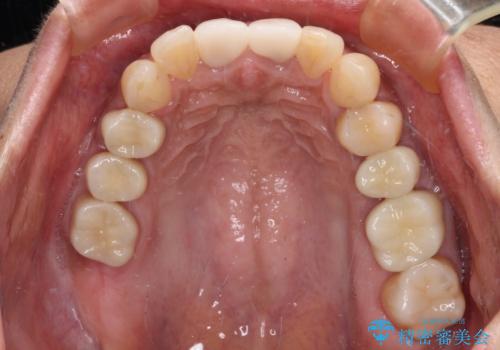

咬み合わせを改善するに当たって、抜歯しなければならない歯や歯列の改善が必要な箇所があったため、矯正治療やインプラント治療から始めていくこととしました。

不自然なくらい真っ白にしたいとのことでしたので、透明感のないフルジルコニアクラウンを用いて補綴することとしました。